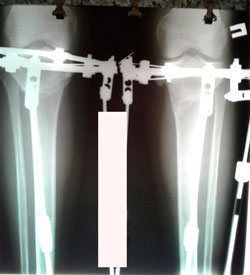

Исходник - 42 года.

Дата операции - 27.05.2020

Красивые ноги получились!